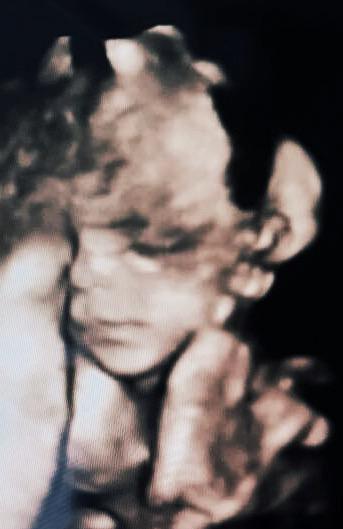

Holky, kdyby jste některá měla zájem 😉